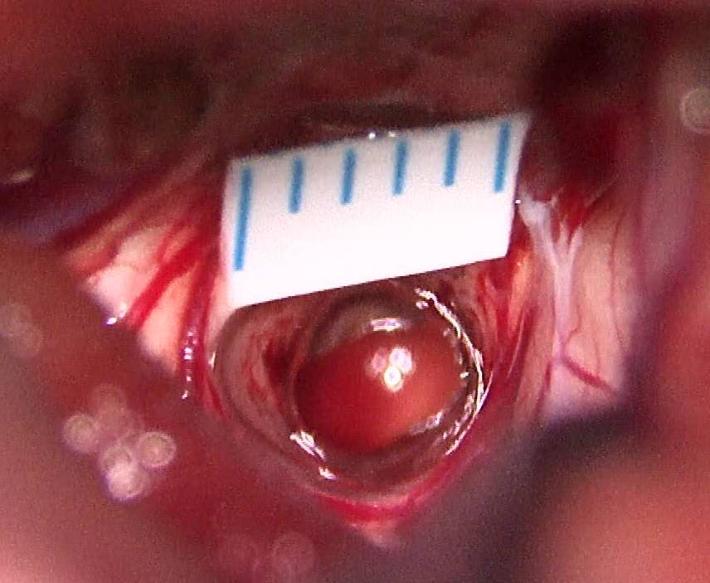

脑干造瘘口控制在2-3毫米,全切除肿瘤并打通中脑导水管

病理星形细胞瘤2级

术后肿瘤全切除,病人眼睛可睁开,四肢活动好,无脑积水